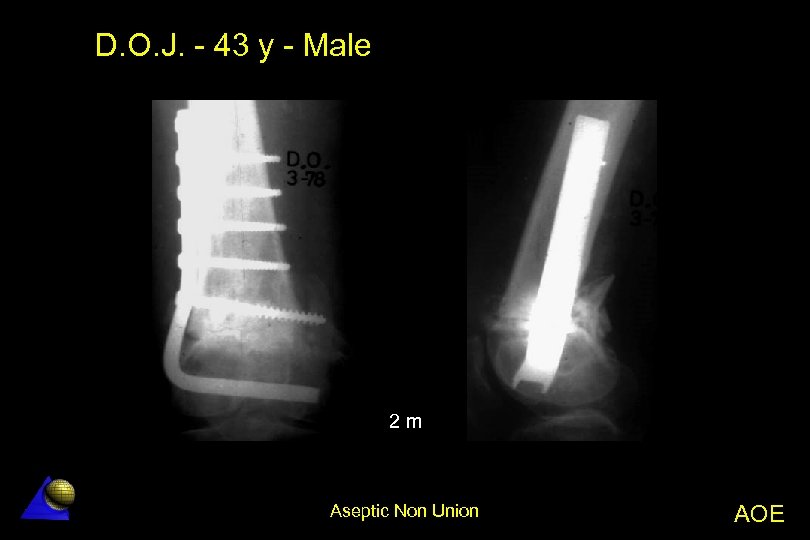

D. O. J. - 43 year old - Male Distal femur non-union - 1. 78 Distal femur metaphyseal non-union l Previous orthopaedic treatment in traction l Angle plate (95º) fixation l Bone healing in 3 months l Aseptic Non Union AOE

D. O. J. - 43 y - Male PO Aseptic Non Union AOE

D. O. J. - 43 y - Male 2 m Aseptic Non Union AOE

D. O. J. - 43 y - Male 10 m 16 m Aseptic Non Union AOE